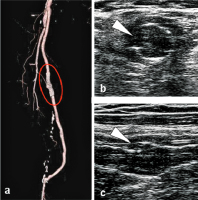

Stentfraktur Typ III

Abbildung 6a-c: Pseudoaneurysma bei Stentfraktur Typ III in der bildgebenden Diagnostik. (a): Kontrastmittelverstärkte CT-Angiographie (VRT); (b): sonographische Darstellung der Stentfraktur Typ III im B-Mode (Querschnitt) mit Visualisierung der Kontinuitätsunterbrechung des Stents (weißer Pfeil), links lateral thrombosiertes Pseudoaneurysma; (c): sonographische Darstellung (Längsschnitt) der Stentfraktur Typ III (weißer Pfeil).

Keywords: CT-AngiographieSonographieStentfraktur